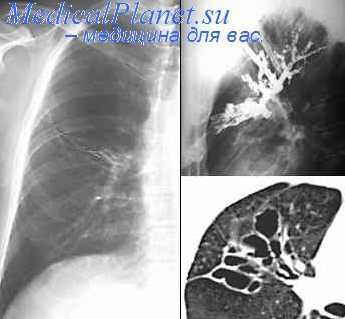

Бронхография – рентгенологическое исследование бронхиального дерева, которое проводится после введения в бронхи рентгенконтрастного вещества, изготовленного на основе йода. После того, как контраст обволакивает стенки бронхов изнутри, они становятся хорошо заметны на рентгеновских снимках.

Цель исследования:оценить состояние просвета бронхиального дерева, а также о полостных образованиях, сообщающихся с бронхами.

· Контраст должен равномерно заполнить бронхи и распределиться по их стенкам. Для этого пациента несколько раз переворачивают, придавая ему разные положения.

· Затем выполняют серию рентгеновских снимков. После этого исследование закончено.